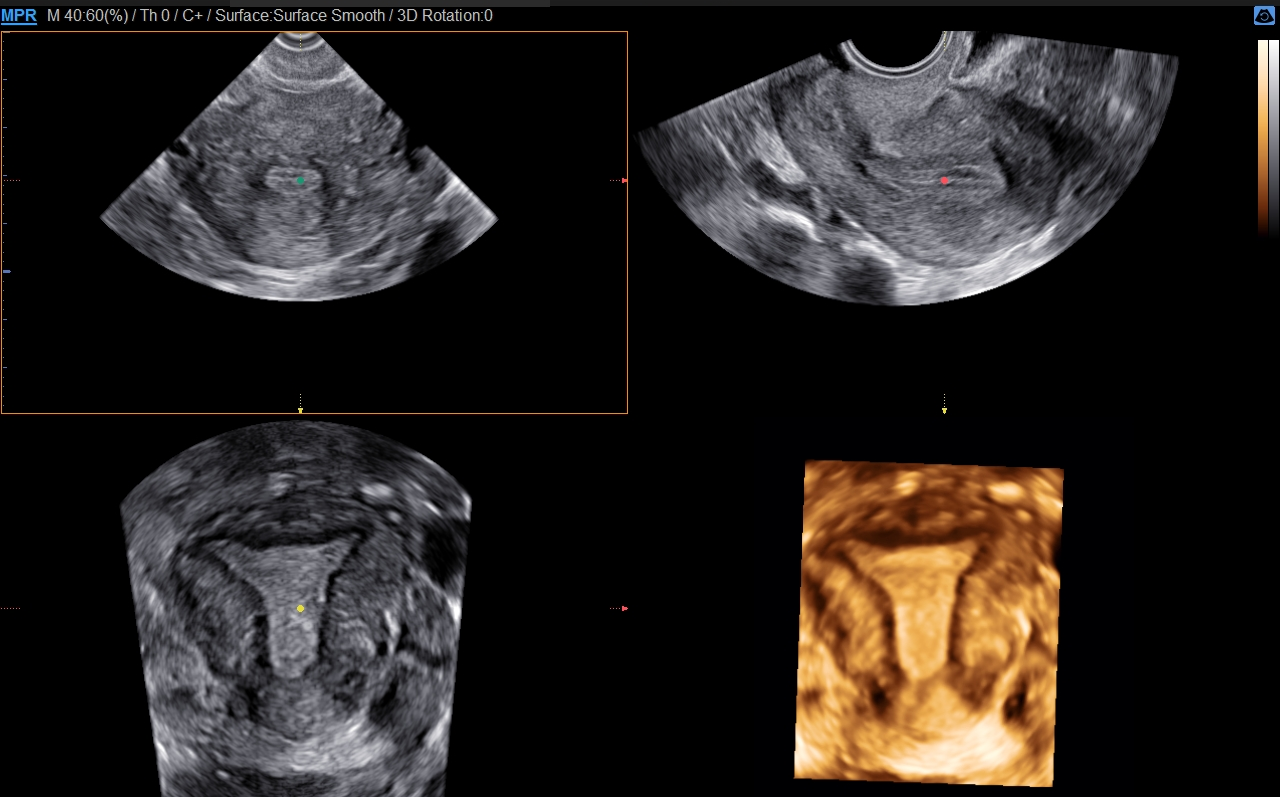

S-Fusion ™ pro prostatu

Pomáhá při přesném cílení během biopsie prostaty

S-Fusion ™ pro prostatu umožňuje bezpečnou navigaci a přesné cílení během biopsie prostaty na základě 3D modelů vytvořených z datových sad MR a také poskytuje funkci pro hlášení polohy biopsie.

Positioning Auto

Positioning Auto pomáhá rychlému a efektivnímu vyšetření. Počáteční registrace mezi CT/MR a ultrazvukovým obrazem probíhá v jednom kroku, umístěním sondy do pacientovy oblasti solar plaxus před skenováním pacienta.